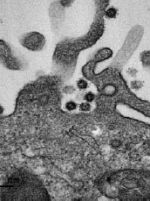

Vignette (© Philippe Roingeard et Sébastien Eymieux, Université de Tours).